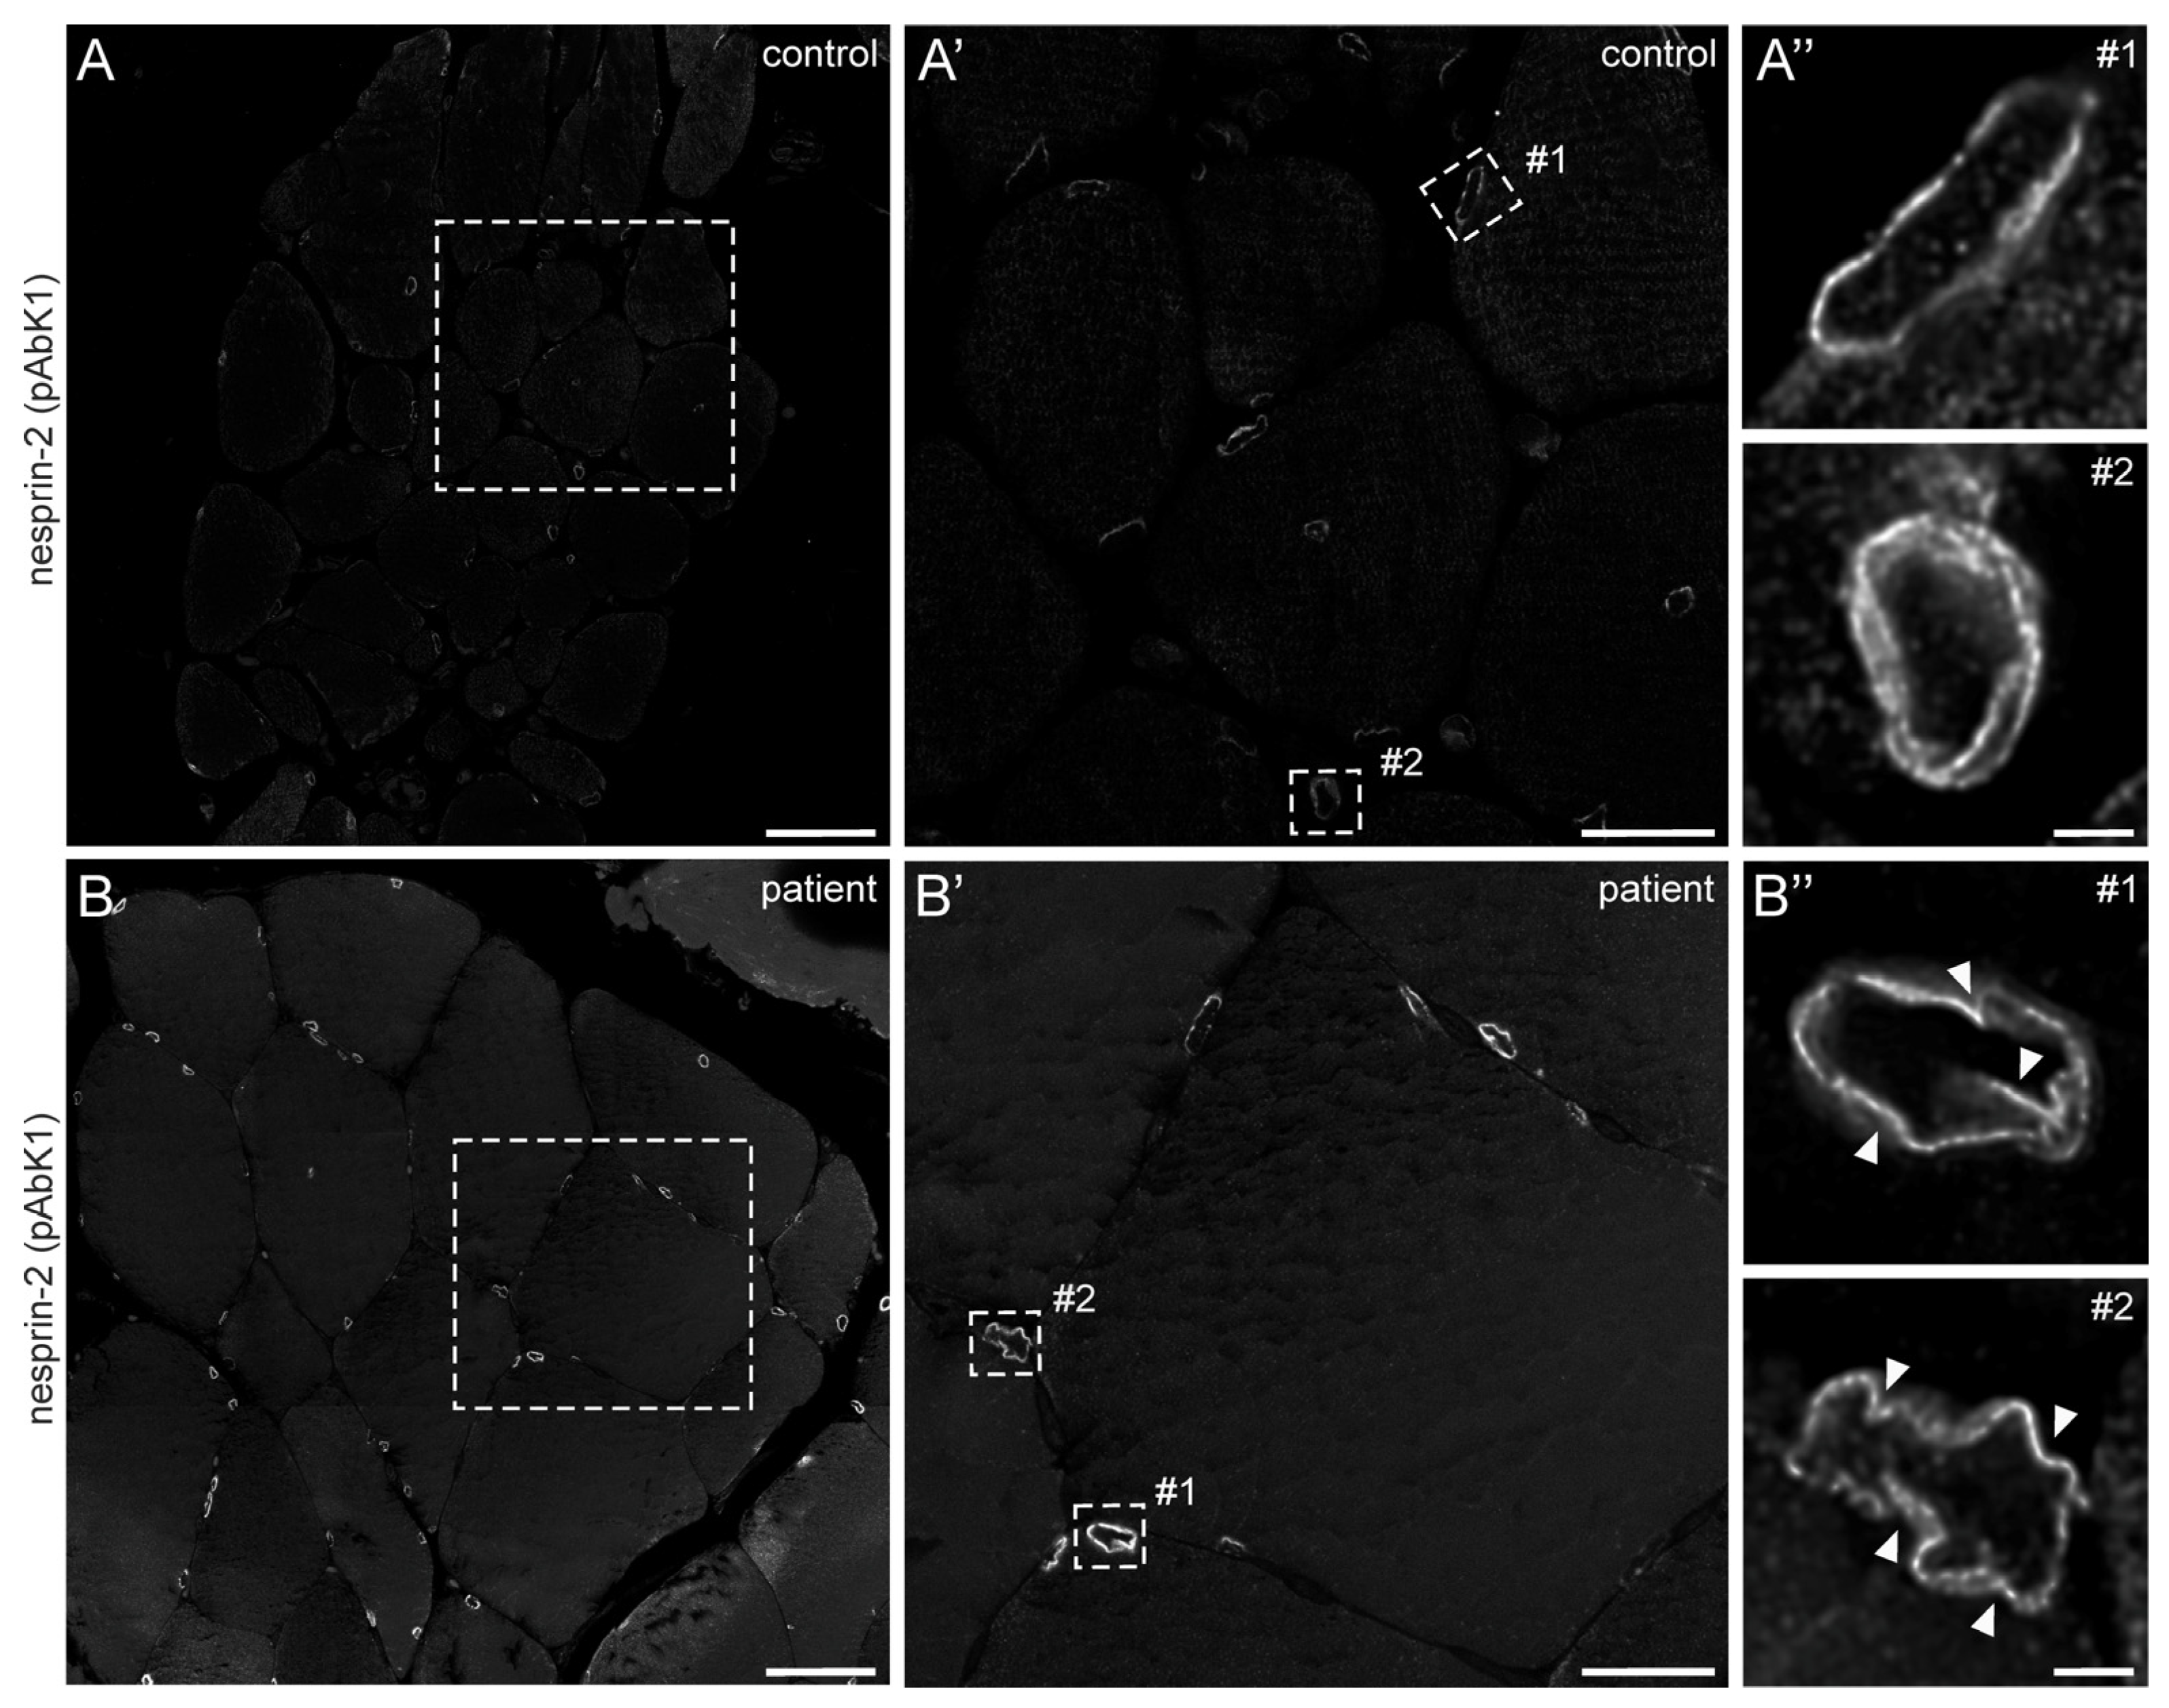

2.1.4. Muscle Biopsy Findings and Molecular and Cell Biology Examinations

4.2. Immunofluorescence (IF) of Cells and Skeletal Muscle Paraffin Sections